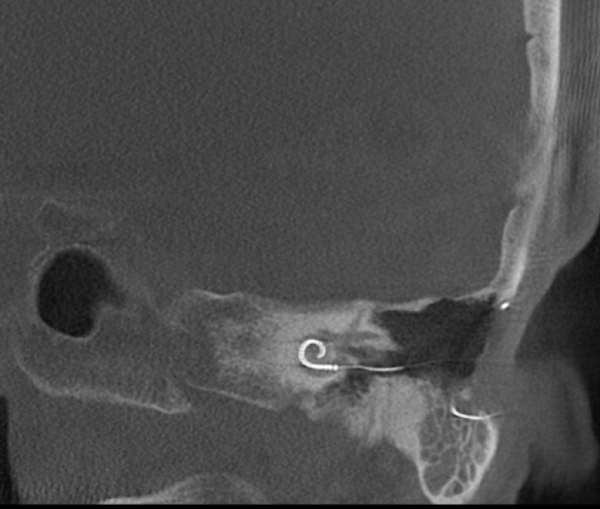

Both patients were imaged immediately with CBCT using SCANORA® 3Dx (Soredex, Tuusula, Finland). The field of view (FOV) was 140 x 165 mm and voxel size 0.2 mm. Imaging parameters were 90 kV, 8 mA, 4.00s. Standard 1 mm axial, coronal and sagittal reformations were made, as well as MIP and 3D reconstructions using OnDemand3D™ software (Cybermed, Seoul, South Korea).

CBCT proved to be optimal for imaging of these implants because of the superior bony delineation and nearly artefact free images. All four parts, i.e. the receiver stimulation part, extracochlear electrode implanted on the surface of the temporal bone, the extracochlear electrode plate and the intracochlear electrode array could be well imaged with CBCT.

On CBCT all four of the important parts of the implant were very well seen both on the axial slices and three dimensional surface reconstruction images. The implant is placed on magnetic plates, and the extracochlear part was seen in an abnormal separated position. The intracochlear electrode array showed no signs of separation in either of the cases. The intracochlear electrodes were well seen in both of the cases.

The optimal images of these two patients are shown in the radiographic illustrations in Figures 1-7.

Figure 6: Sagittal thick MIP image of the implant of patient 2.

Figure 7: Patient 2 - Sagittal oblique image of the intracochlear portion of the implant.